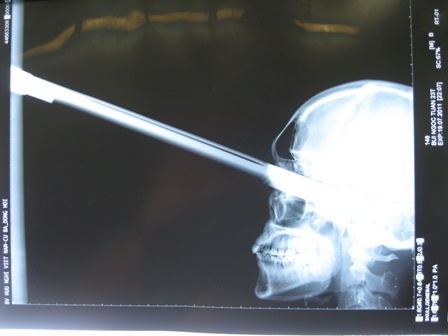

(Dân trí) - Ngày 20/7, tin từ BV Trung ương Huế vừa cứu sống bệnh nhân nam Bùi Ngọc T. (23 tuổi, quê ở huyện Hoằng Hóa, tỉnh Thanh Hóa) sau khi bị một cây kiếm dài đâm xuyên vào mắt trái 9,5cm gần chạm đến não.

Được biết, nạn nhân bị hại khi đang đi du lịch tại TP Đồng Hới, Quảng Bình lúc 21h tối 19/7. Kết quả chụp phim X-quang cho thấy mũi kiếm đâm thẳng vào hốc mắt, vào tận nền sọ, sâu khoảng 9,5cm.